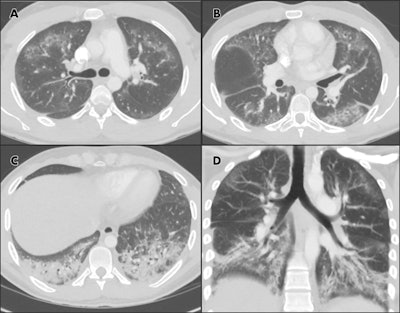

Chest CTA images in 24-year-old man with a history of e-cigarette use. A-C, select axial sections of the lung presented on lung windows reveal patchy ground-glass opacities distributed bilaterally with some, A, B, subpleural sparing and, C, consolidation in the lung bases. D, coronal oblique thick-slab average intensity reconstruction shows the predominance of the findings in the basal lungs and demonstrates the peripheral subpleural sparing. Images courtesy of RSNA.

Radiography findings on chest x-ray were nonspecific, consisting of bilateral and basilar predominant opacities; on CT these were confirmed to be a combination of ground-glass opacities and consolidation. Clinicians also observed relative preservation of the subpleural regions of the lungs, another feature reported in the Wisconsin and Illinois cases.

Abbarra and Kay believe that this latter phenomenon could be related to the main involvement of the central aspect of the secondary pulmonary lobule, which is believed to be a response to an inhaled agent.